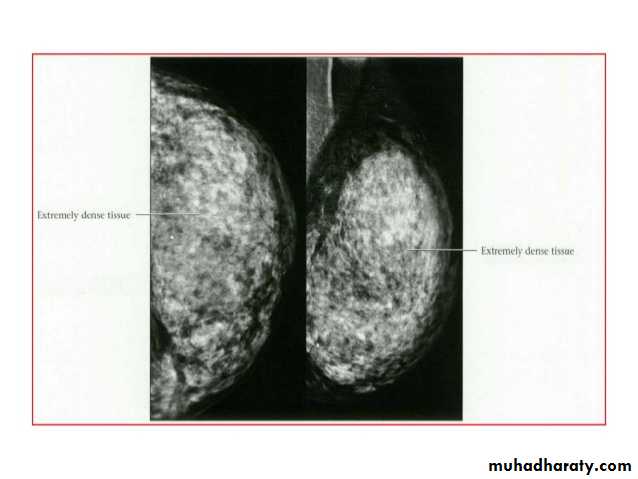

Breast density & who can U detect a mass lesionYour mammogram report must take in consideration & assessment the breast density. Breast density is based on how fibrous and glandular tissue tissues are distributed in your breast, vs. how much of your breast is made up fatty tissue.

Dense breasts are not abnormal, but they are linked to a higher risk of breast cancer. We know that dense breast tissue can make it harder to find cancers on a mammogram. Still experts do not agree what other tests, if any, should be done in addition to mammograms in women with dense breasts who aren’t in a high-risk group (based on gene mutations, breast cancer in the family, or other factors